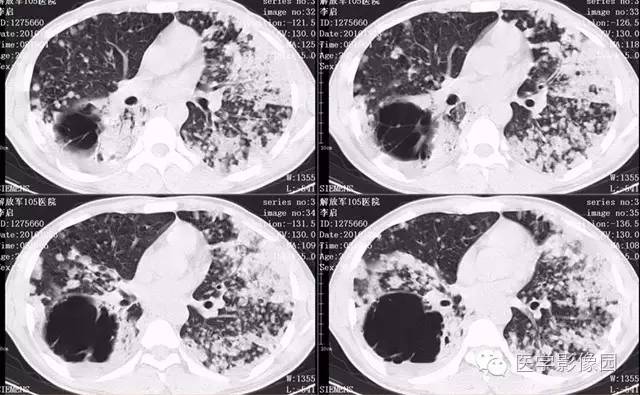

弥漫性肺泡细胞癌1例CT影像表现

病理结果:弥漫性肺泡细胞癌

弥漫性肺泡癌的主要临床及CT表现:临床表现无明显特征, 随着病情的进展, 咳嗽、 咳白痰、 进行性气促。CT表现 为病变分布有两种情况:病变累及一个肺段或肺叶;病变广泛分布于两肺。可归纳为5个特征性征象:蜂房征;支气管充气征;磨玻璃征;血管造影征;两肺弥漫分布的斑片状与结节影。